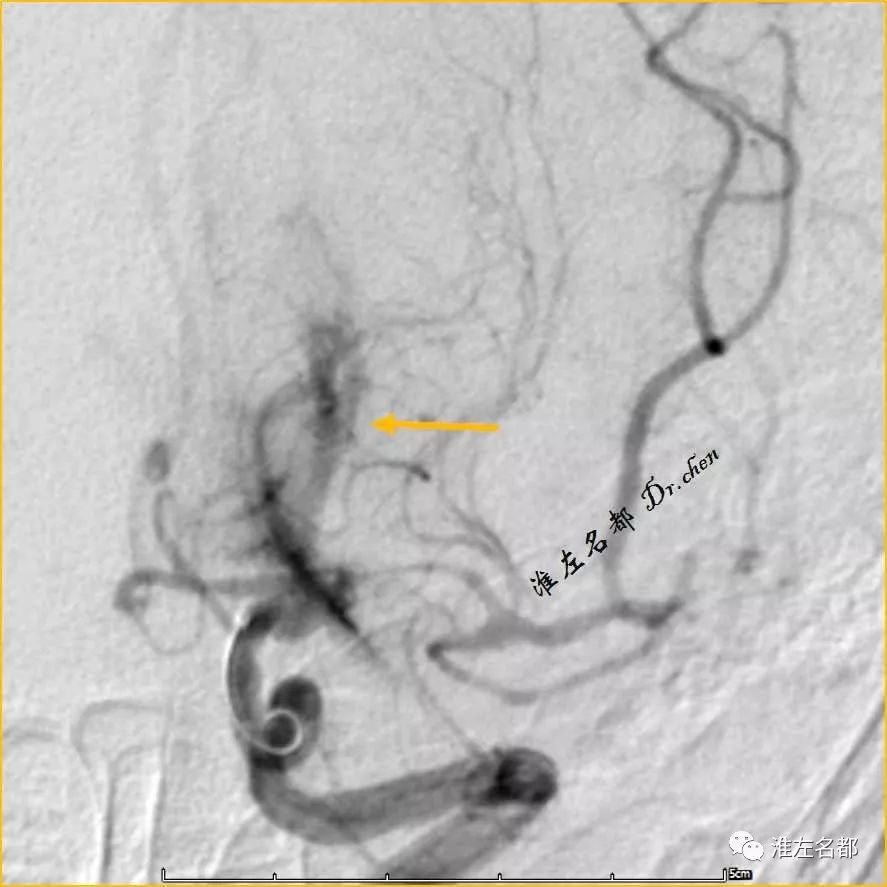

△DSA:右侧MCA主干闭塞

△DSA:取栓治疗后,右侧MCA闭塞再通,M1局部狭窄(橙箭)